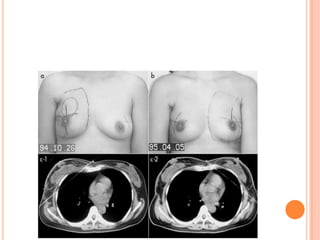

More normal tissue is being irradaited. (lung, heart and

contralateral breast)

1. Extension oftangential fields– by extending medial border – 3cm across midline or by using imaging techniques 2. Separate field – • Medial border – midline , matching with tangential field border • Lateral border – 5-6cm from midline • Superior border – abuts inferior border of supraclav field or at 1st ICS (superior border of head of clavicle) if only IMNs are to be treated • Inferior border – at xiphoid or higher if 1st three ICS covered

• 28.

More normal tissueis being irradaited. (lung, heart and contralateral breast)